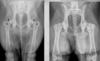

What are Retained endochondral cartilage cores?

Disturbed ossification phenomenon seen in

Young large or giant dogs.

Most commonly distal metaphysis of ulna.

Cause unknown for certain. Overnutrition, food additives theorized.

Bilateral symmetrical changes

Shortening of general length, mimics traumatic premature closure of growth plate.

In the image: the flame shaped radiolucent area with sclerotic rim.

What are nutrient foramens?

Foramens superimposed on medullary cavity.

Fractures aren’t symmetrical so if the exact same mark is in the same spot in both limbs, consider nutrient foramens.

In the image: the thin dark lines. There is also a Mach line to the left of the nutrient foramen.